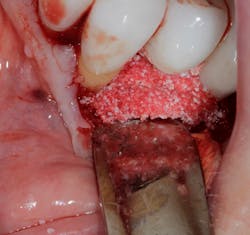

Another scenario that took place in a private practice with actual dollar amounts can be seen in treatment plan C. This patient had already paid for treatment plan B in the $5,000–$7,000 range and subsequently presented to the practice with moderate peri-implantitis. In addition to the money the patient had already invested, she would now be responsible for the financial costs of treatment plan C.

After reviewing the additional costs and lengthy healing time involved with surgery to correct the ailing implant, the overall costs associated with treatment were in the $8,000–$10,000 range, with more than three years of treatment time invested. Of important note is that most insurance companies limit the amount of reimbursement for implant-related services. When dealing with insurance companies, accurate ADA coding and claims submission are critical to facilitate services and expedite reimbursement.